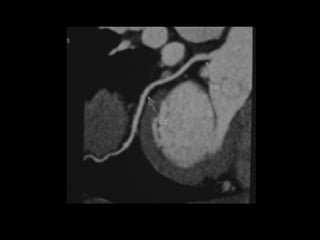

Radiographers use medical imaging equipment like X-rays and MRIs to produce images of patients' internal structures and organs. They are responsible for positioning patients, operating scanning machines, and ensuring quality images. Radiographers must have strong attention to detail, excellent communication skills, and the ability to work well under pressure to accurately capture anatomical features and diagnose any abnormalities.